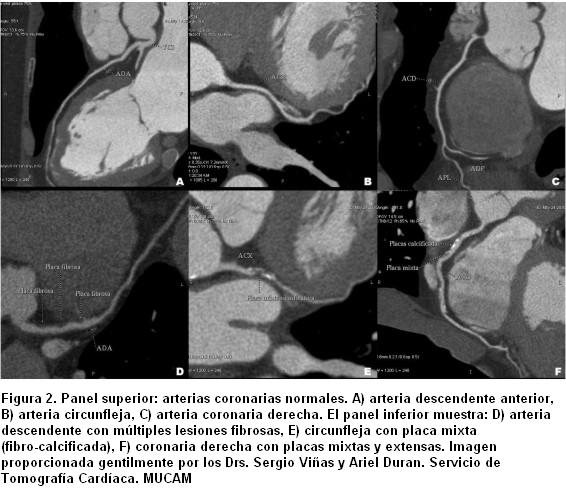

Identificación de estenosis coronaria

Por otro lado, el problema de la angioTC es que los resultados están limitados a vasos relativamente grandes ³ 1,5 mm, pues la visualización no incluye los vasos más pequeños y sus ramas, lo cual disminuye su sensibilidad. Los objetos de alta densidad, como las placas de calcio coronario y los stents, limitan su capacidad para delinear el grado o la presencia de estenosis (31,32). Para fines clínicos una angioTC normal excluye la EC obstructiva y la necesidad de otras pruebas diagnósticas, catalogando al paciente como de bajo riesgo. Sin embargo, dado su menor VPP para definir la severidad de la estenosis y predecir la alteración del flujo coronario (33,34), una angioTC anormal puede provocar incertidumbre en la indicación de una coronariografía o un procedimiento de revascularización (35).